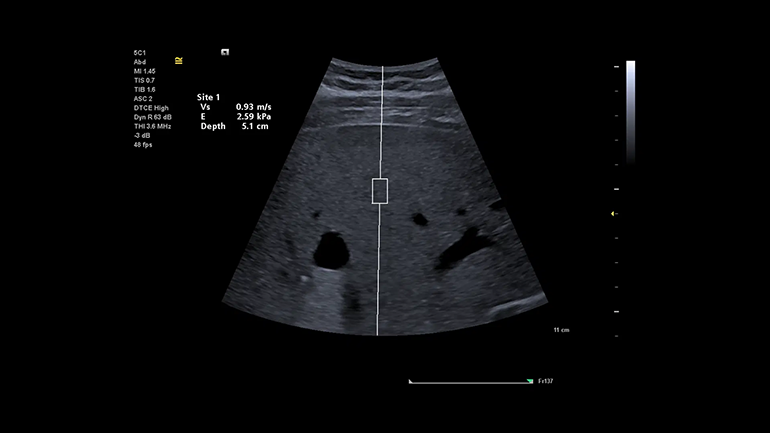

Стресс-эхокардиография. Функция стресс-эхокардиографии включает в себя комплекс инструментов и измерений для получения данных о циклах сердечной деятельности на различных этапах стресс-эхокардиографического исследования, просмотра, выборочного сравнения, оценки и архивирования наборов кинопетель с ЭКГ-синхронизацией. Технология оценки скорости распространения поперечной волны и эластичности в выбранной области интереса (Virtual Touch quantification). Метод измерения скорости поперечных (сдвиговых волн) в режиме реального времени, в котором используются низкочастотные акустические импульсы (ARFI), генерируемые непосредственно ультразвуковым датчиком. Оценка скоростей сдвиговых волн в выбранной врачом зоне интереса коррелирует с показателями жесткости ткани.

Технология оценки скорости распространения поперечной волны и эластичности в выбранной области интереса (Virtual Touch quantification). Метод измерения скорости поперечных (сдвиговых волн) в режиме реального времени, в котором используются низкочастотные акустические импульсы (ARFI), генерируемые непосредственно ультразвуковым датчиком. Оценка скоростей сдвиговых волн в выбранной врачом зоне интереса коррелирует с показателями жесткости ткани. Технология качественной визуализации относительной эластичности ткани eSie Touch. Метод качественной и количественной эластографии в режиме реального времени, который позволяет вычислять и отображать на экране относительную жесткость исследуемой ткани. Метод eSie Touch дает возможность сгенерировать эластограмму за счет применения к ткани последовательных циклов мануальной компрессии во время стандартной визуализации в B-режиме.